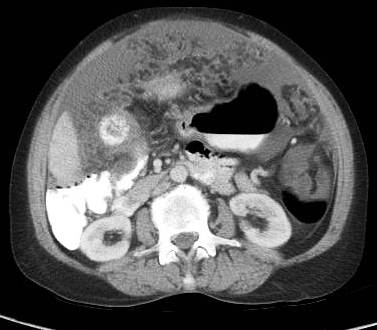

Invasion of duodenum, hepatic flexure, lesser sac and antro-pyloric region

Majority of tumors are inoperable at the time of diagnosis and average survival is only six months after first symptoms appears. The rich lymphatic and venous drainage of gallbladder allows rapid spread to lymph nodes and widespread dissemination. There is local spread to duodenum, stomach and colon (Figure 8-11).

Figure 8: Advance case showing invasion of hepatic flexure of colon and also involving the antro-pyloric region medially